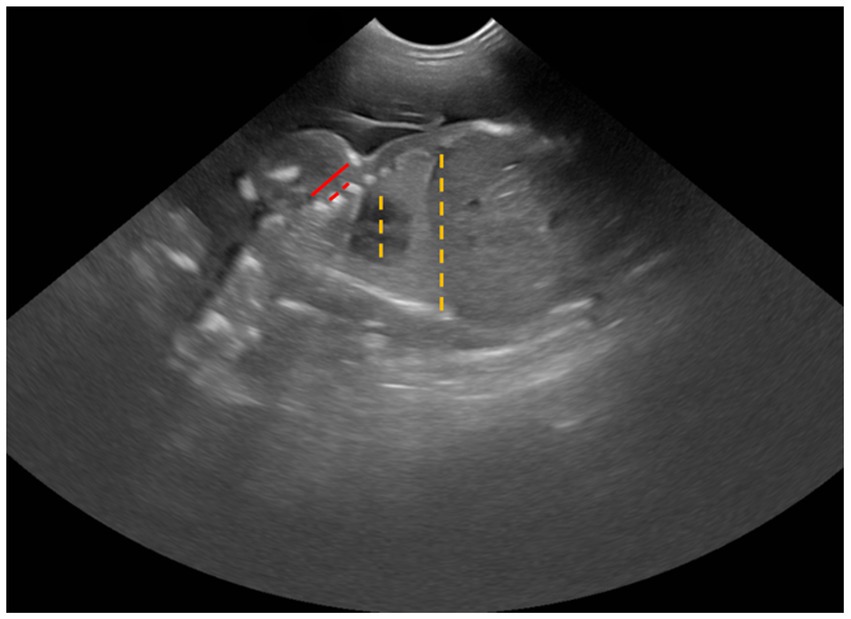

3. Cardio-thoracic ratio (CTR) was calculated by measuring the largest distance at the middle level of the fetal heart (outer-to-outer edge) and then dividing by the longest distance at the middle level of the last rib (Figure 2). Both measurements were done in a dorsal plane sonograph.

1. Intercostal space (ICS) was determined by measuring the distance from the caudal edge of the first rib to the cranial edge of the fourth rib, subtracting the diameters of the second and third ribs, and then dividing that total by three (Figure 2).